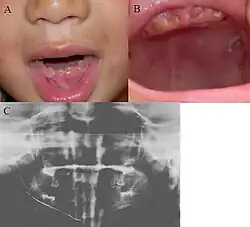

| Oral photographs from an individual with Dentinogenesis imperfecta | |

People with this condition have abnormal enamel, short and narrow roots, and can lack nerves. This condition can cause teeth to be discolored (most often a blue-gray or yellow-brown color) and translucent, giving teeth an opalescent sheen.[2][3][8][5][9] Teeth are also less mineralized than normal, making them prone to rapid wear, breakage, and loss.[2][3][4][5][8] These problems can affect primary (baby) teeth alone, or both baby teeth and permanent (adult) teeth, with the primary teeth usually more severely affected.[5][8]

- Discolored teeth - teeth may be amber, brown, blue or opalescent

- Bulbous shape to the tooth crown due to cervical constriction

- Tooth wear/Non-carious tooth surface loss (NCTSL) - due to the poorly mineralized dentin, the enamel of the tooth is unsupported and subsequently shears or chips off as it is subjected to occlusal (biting) forces. This exposes the underlying less mineralized dentin which is less resistant to wear. Therefore, features of abrasion and attrition may become apparent.

The primary (baby) teeth are usually more severely affected than permanent (adult) teeth.[3][5][8]

Radiographic presentation

Radiographic features include:

- Bulbous shape of tooth crown with pronounced cervical constriction

- Small pulp, or total pulp obliteration

- Small or obliterated root canal

- Presence of pulp stones

- Narrow and small roots

- Periapical radiolucency without any evidence of clinical pathology such as tooth decay (dental caries)[2][3][5][14]